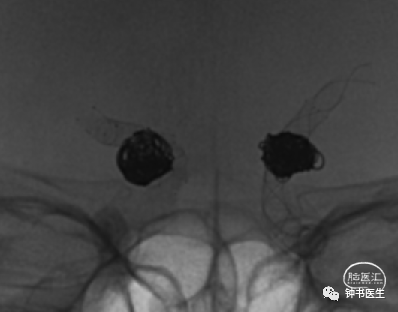

2015-06-26,蛛血,DSA示双侧后交通动脉瘤,左侧为责任动脉瘤,行支架辅助左侧后交通动脉瘤栓塞(LVIS 4.5-20,8枚弹簧圈)。

2015-11-03行右侧后交通动脉瘤LVIS+弹簧圈栓塞,左侧动脉瘤瘤颈残留,未处理。

2018-06-06左侧后交通动脉瘤Pipeline 4025植入。